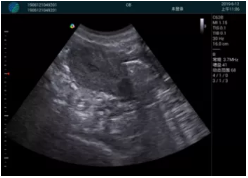

M20查看:囊內(nèi)回聲均勻,邊界清晰,囊壁光滑

M20引導(dǎo)抽吸術(shù)后囊腫消失,原區(qū)域空腔形成,脂肪層與腺體層架構(gòu)發(fā)生改變

超聲引導(dǎo)下可視化人流是技術(shù)安全性的保障,一般對人流術(shù)設(shè)備預(yù)算不高,M20具備婦產(chǎn)科軟件包,且穿透力圖像質(zhì)量好,既滿足人流引導(dǎo)需要,也可用于床旁超聲的需求。